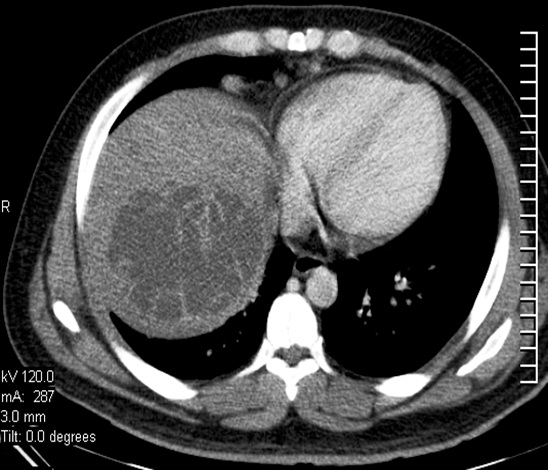

TERATOMA DE OVARIO

Antonio Alvarado Armuelles, Emanuel Tejeira

46-47